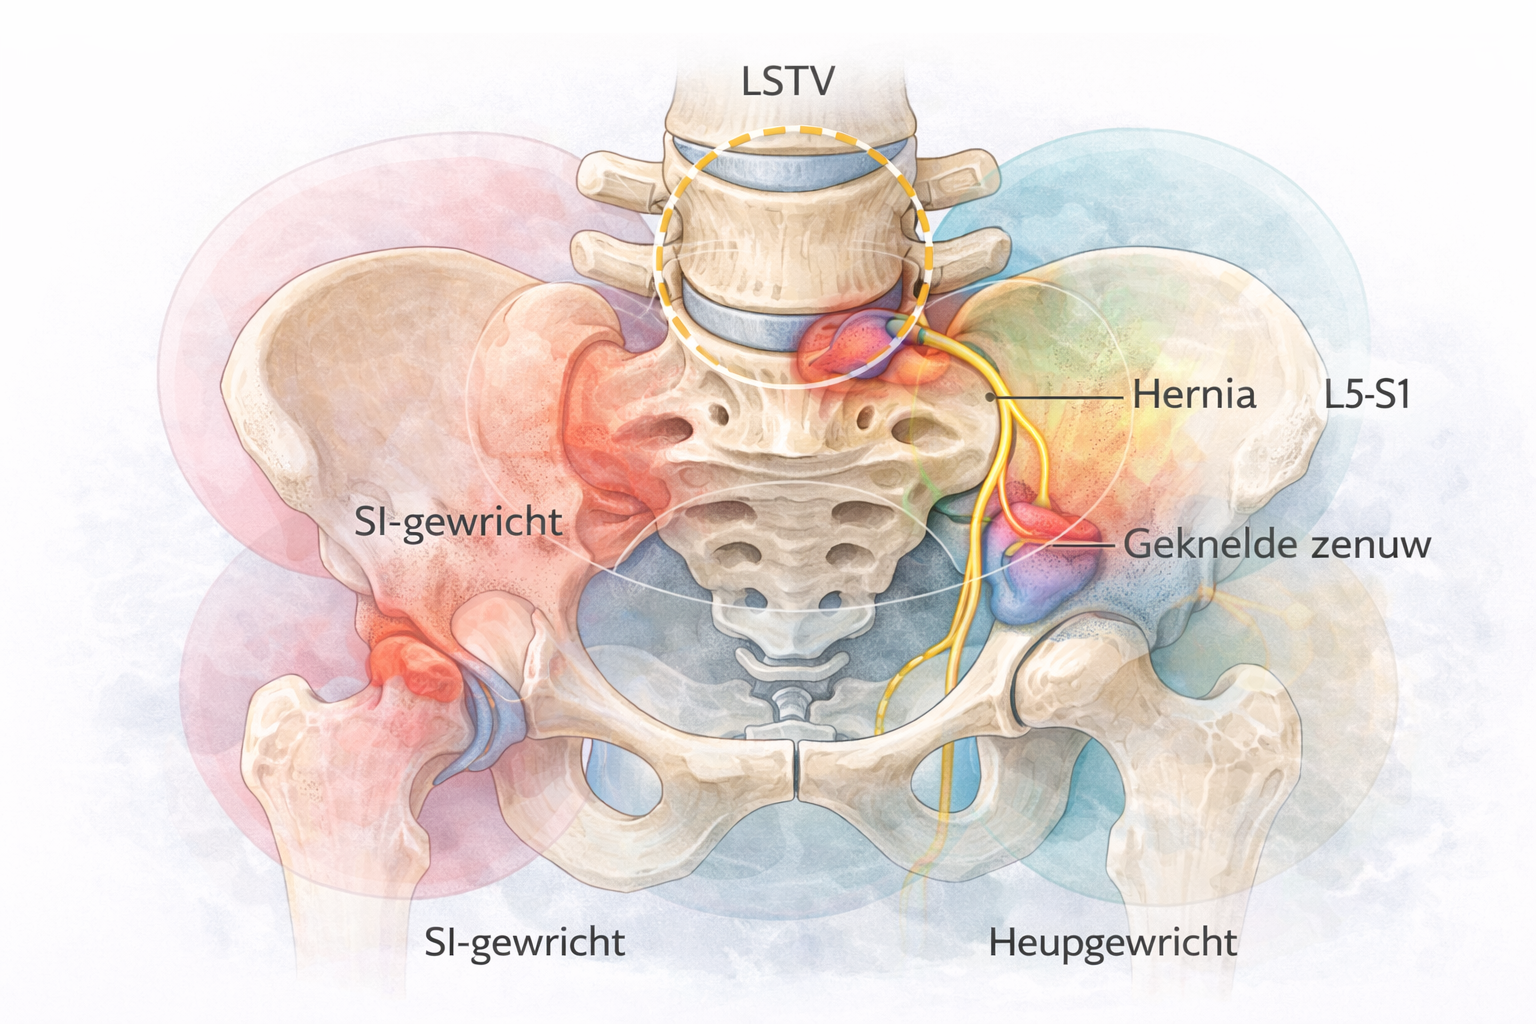

Bij patiënten met lage-rugklachten en een vastgestelde of vermoede LSTV is een zorgvuldige differentiaaldiagnose essentieel.

De aanwezigheid van een LSTV vergroot het risico dat klachten te snel aan deze anatomische variatie worden toegeschreven. Dit kan leiden tot gemiste diagnoses, een te smalle klinische blik en onnodige medicalisering.

Lage-rugpijn is per definitie multifactorieel. Ook bij aanwezigheid van een LSTV blijven andere oorzaken minstens even waarschijnlijk.

Hoewel een LSTV soms wordt geassocieerd met uitstralende pijn, past het klachtenpatroon niet altijd bij een klassiek radiculair beeld.

Te overwegen:

Hernia nuclei pulposi

Radiculopathie door stenose

Perifere zenuwcompressie

Plexusproblematiek

Een discrepantie tussen neurologische symptomen en het beeld van de overgangswervel vraagt om herbezinning en mogelijk aanvullende diagnostiek.

Pijn rond de lumbosacrale overgang kan ook afkomstig zijn van structuren in het bekkengebied.

Te overwegen:

Sacro-iliacale gewrichtsdysfunctie

Pseudo-articulaties bij LSTV kunnen klinisch overlappen met SI-gerelateerde pijn, maar zijn niet gelijk te stellen.

Heup- en weke-delenproblematiek kan zich presenteren als lage-rugpijn.

Te overwegen:

Coxartrose

Femoroacetabulair impingement